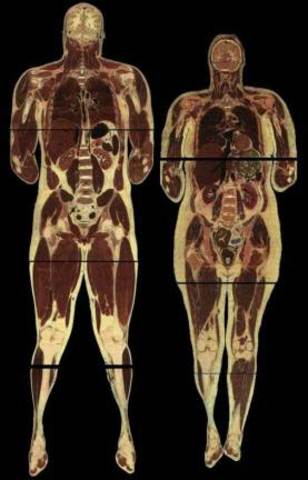

• Visible Human Project®

Visible Human Project®

Em 1986, a National Library of Medicine do National Institutes of Health, nos Estados Unidos, lançou o Visible Human Project®, projeto que propunha a virtualização de um corpo humano masculino, inicialmente, seguido por um corpo humano feminino, disponibilizando-o em uma plataforma de acesso, inaugurando uma nova proposta nas pesquisas e no ensino-aprendizado da anatomia (USNLM, 2008).

• Anatomia como linha de pesquisa e área de conhecimento

A Anatomia Humana se consolida como linha de pesquisa e área de conhecimento com o correr dos séculos, porém, o final do século XX e início do século XXI propõem ao docente-pesquisador um re-olhar sobre seu objeto de pesquisa, inaugurado pelo Visible Human Project®, resignificando-o a partir da nova tendência da produção e transmissão do conhecimento, que Alvin Toffler (1990) designa de terceira onda da produção humana: a sociedade da informação e conhecimento.